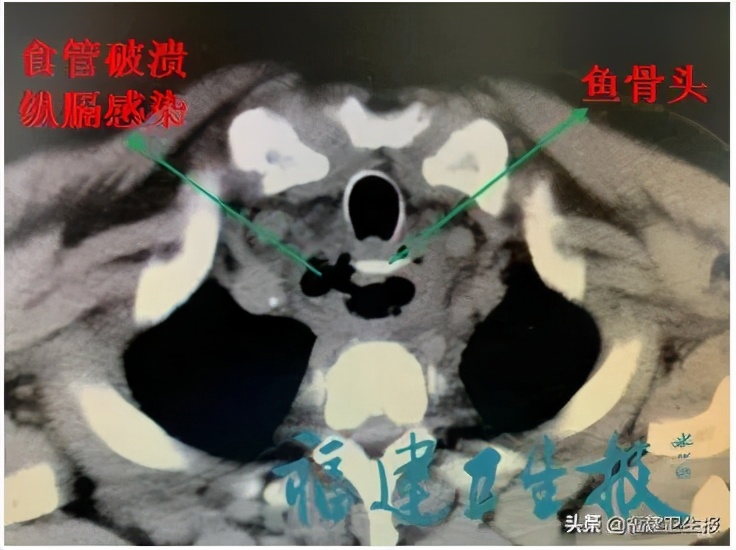

接诊的医生一检查,发现鱼骨已经不在咽喉部了,为了“追踪”它的去向,医生让魏先生做了个CT,结果让大家吓一跳:鱼骨头卡在胸上段食管处,而且一端已经穿透食管,扎入右侧纵隔!

若不及时处理,鱼刺可能刺到两侧的大血管,并导致纵隔感染进一步加重,由此可能形成全身感染,休克、死亡。